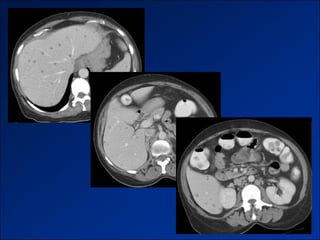

Hình ảnh trên CLVT

- Giai đoạn sớm:

+ Gan to.

+ Tăng tỷ trọng do xơ hóa.

- Giai đoạn muộn:

+ Gan biến đổi hình thái và đường bờ.

+ Dấu hiệu tăng ALTMC.

+ Dấu hiệu khác:

Dịch ascite – Lách to – Dày thành TM.

Nốt tân tạo.

Biến chứng (HCC).